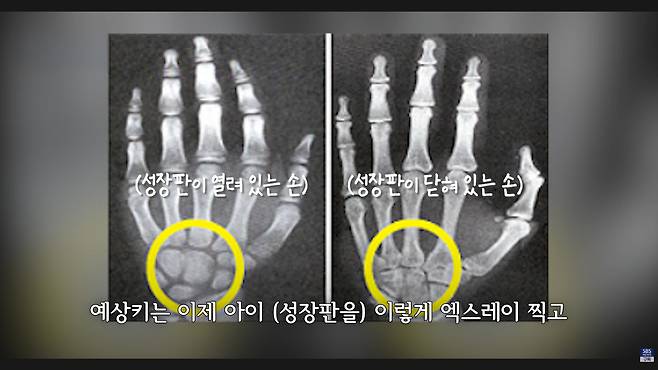

아빠 키와 엄마 키를 더해서 하는 거는 정말 추정치인 거고, 만약에 그게 맞다면 사실은 형제자매가 다 키가 똑같아야 되는데 그렇지 않잖아요. 이거는 사실은 경향을 보는 것뿐이고, 성장판을 찍는 거는 요새 높게 보고하는 데는 95%까지 보고합니다. 꽤 정확해요.

몸이 좀 커지고 말단 비대증이라고 해서 손이랑 턱이 커지죠. 암도 발생할 수 있고. 성인은 더 심각한 부작용이 생기기 때문에 절대 하면 안 되는데, 그런 작동을 하기 때문에 키도 크는 거죠. 어렸을 때는 성장판이 열려 있으니까.

성장이 끝나기 전에 맞아야 돼요. 사춘기가 시작되기 전. 사춘기 땐 엄청나게 성장호르몬이 나오기 때문에 그때 맞는 건 의미가 없거든요. 사춘기 전에 맞아야 됩니다.